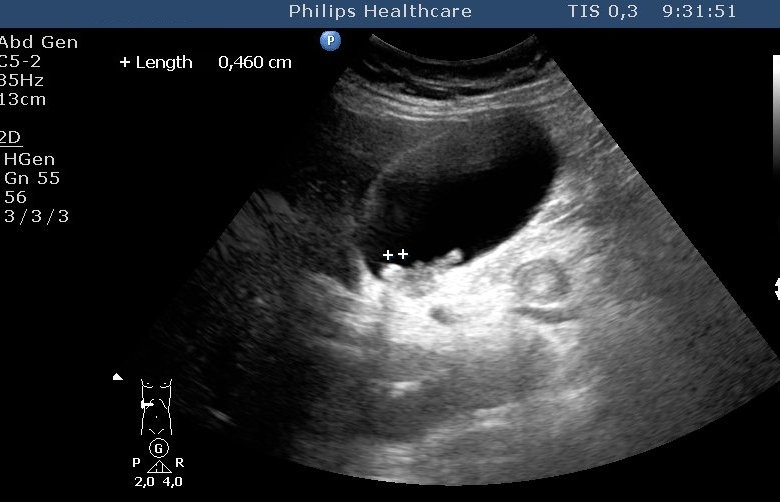

Figure 16: Simple liver cyst, US

Differentialdiagnostic difficulty is only given if the liver cysts show atypical appearence (its content becomes more hyperechogenic in US or more hyperdense in CT). In this situation, the differentiation from cystic tumor, metastasis or probably abscess is possible only if taking into account the clinical data and performing US or CT-guided punction.